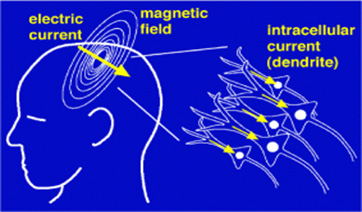

Our bodies are electromagnetic. This is why our brains work and why our heart beats and our muscles contract. As Michio Kaku, CUNY physicist, futurist, and author says, “Our brains are milliwatt transmitters.” Nature, the premier publication in science, notes: “There are striking analogies between signaling networks in biological systems and electronic circuits.”

Electromagnetic fields of all kinds (radiofrequency/microwave, dirty electricity) knock calcium ions off the cell membrane. This accounts for the wide variety of effects seen with exposure to smart meters because calcium acts like a neurotransmitter. Thus, your heart, your gut, your brain, your muscles, and your hormones can be affected. In general, the first place that is harmed is the place where you have the least resistance. Over time, various other organ systems will be harmed. We go into this in great detail on our Health: The Science page.

Why do smart meters cause such a vast array of health effects? The effect of EMFs on calcium can explain the vast majority of health effects, first because calcium plays a critical role in the transmission of nerve signals and secondly because calcium is the glue that holds the cell walls together. EMFs can easily knock the calcium ions off the cell membrane.

An excess calcium causes the transmission of unnecessary nerve signals. This accounts for things like heart palpitations, insomnia, and anxiety, and ADD. You can read about this in greater detail on our Health: The Science page, where we have numerous links to research on this phenomenon.

When calcium is pulled off the cell wall, the cell membrane is weakenedâthe cell becomes leaky. Leaky cell walls cause the blood-brain barrier is breached. The blood-brain barrier protects our brain from toxins. A leaky blood-brain barrier is partly responsible for diseases like Alzheimer’s, dementia, and Parkinson’s. Have you ever wondered why we have seen such a huge climb in the rate of Alzheimer's, dementia, and Parkinson’s disease? Have you noticed how the increase correlates with the proliferation of wireless in our society? The background RF radiation has increased 20,000 times since the 1980s! It’s about 15 years into that that we started to see a really big rise in these diseases.